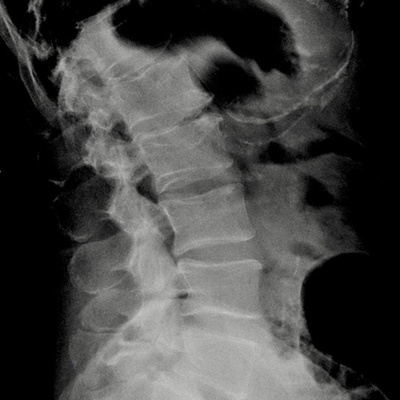

In der Radiologie Hirslanden Zürich wird das gesamte Spektrum der diagnostischen bildgebenden Verfahren angeboten.

- Hervorragende Bildqualität bei extrem kurzen Untersuchungszeiten

- Detaillierte Untersuchungsverfahren mit geringer Strahlenbelastung